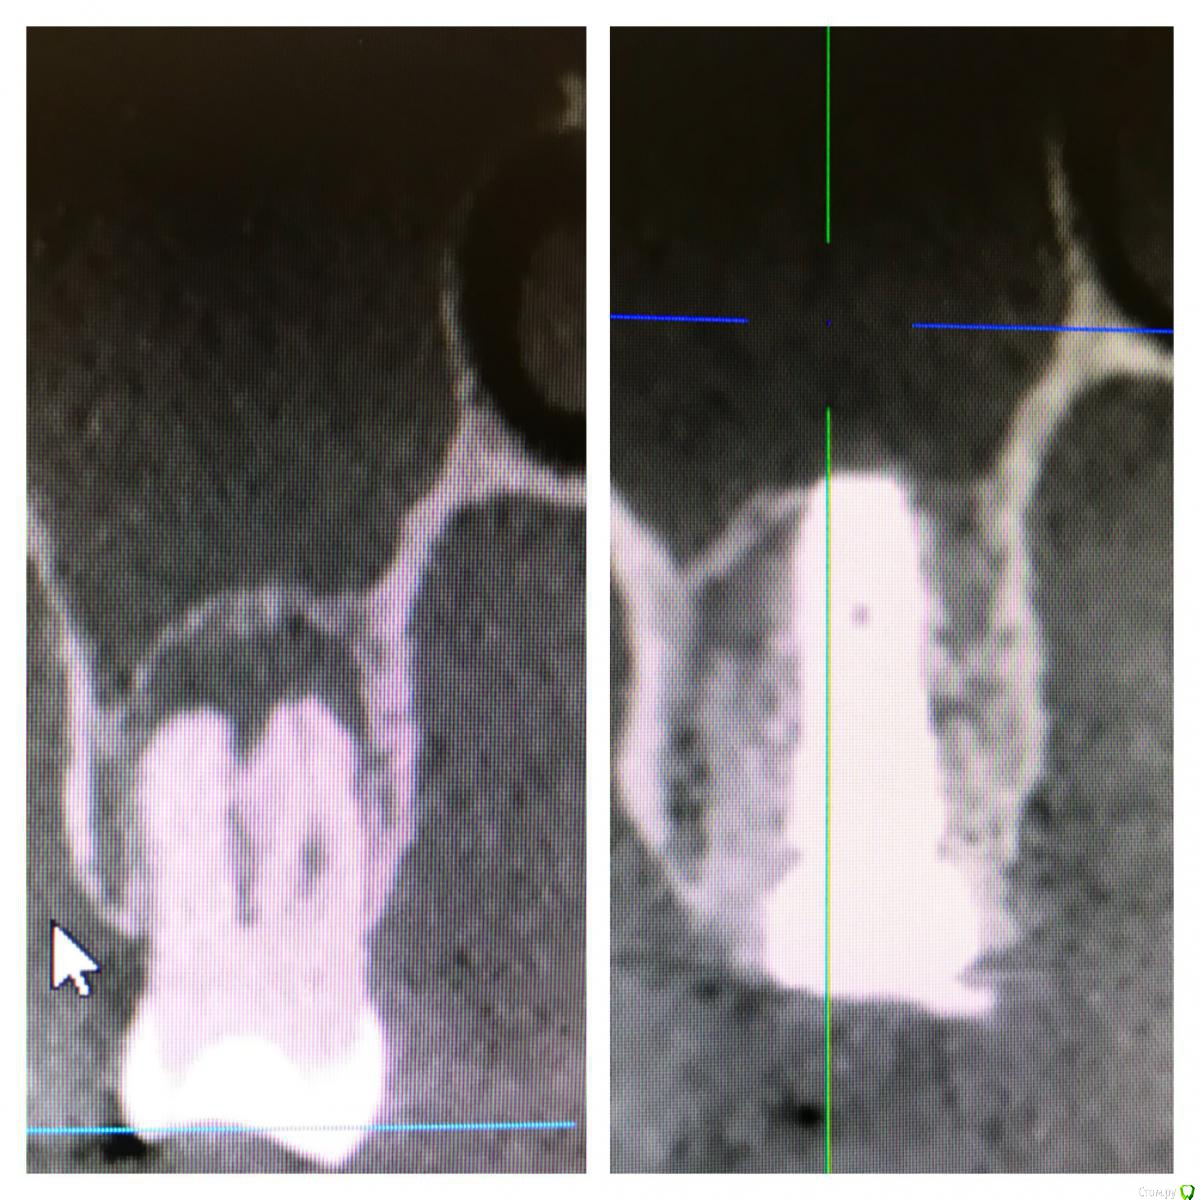

колесников Опубликовано 7 ноября, 2019 Поделиться Опубликовано 7 ноября, 2019 (изменено) всё возможно в этой жизни. Интересно посмотреть такой кейс. Но это смущает а что Вас смущает? Ситуация очень благоприятная,киста сама сделала синуслифтинг,если сделаем паузу-потеряем этот объём Изменено 7 ноября, 2019 пользователем колесников 4 Ссылка на комментарий

Evikrol Опубликовано 10 ноября, 2019 Поделиться Опубликовано 10 ноября, 2019 а что Вас смущает? Ситуация очень благоприятная,киста сама сделала синуслифтинг,если сделаем паузу-потеряем этот объёмКакой протокол имплантации в таком случае, как быть уверенным что инфекции не осталось в полости с гноем? Как вообще правильно? Удалить, обильно промыть эндошприцем, крутить с графтом или без? Кюретажить или нет? Ссылка на комментарий

колесников Опубликовано 10 ноября, 2019 Поделиться Опубликовано 10 ноября, 2019 Какой протокол имплантации в таком случае, как быть уверенным что инфекции не осталось в полости с гноем? Как вообще правильно? Удалить, обильно промыть эндошприцем, крутить с графтом или без? Кюретажить или нет? ну ладно пациенты,но Вы то! Какой гной! Где? Вылущили оболочку-все чисто. Обычно и вылущивать ничего не нужно,вынули зуб ,а на нем висит оболочка. Ревизию по стенкам конечно лучше делать и промыть. Грануляции от жидкости набухают и визуализируются. Лунка под капсулой стерильна. Главное чтобы слюна не попала и не остались грануляции. Я всегда использую графт,тк такой объём сгусток не в состоянии сохранить,распадётся. 1 Ссылка на комментарий

rimtar Опубликовано 11 ноября, 2019 Поделиться Опубликовано 11 ноября, 2019 а что Вас смущает? Ситуация очень благоприятная,киста сама сделала синуслифтинг,если сделаем паузу-потеряем этот объёмкрасивая идея и фото, но как фиксирован имплант? просто лежит в графте? 1 Ссылка на комментарий

Irouil Опубликовано 11 ноября, 2019 Поделиться Опубликовано 11 ноября, 2019 (изменено) красивая идея и фото, но как фиксирован имплант? просто лежит в графте?Бикортикально (вернее - в кортикалке дна пазухи) и в перегородке, там где она осталась. Если широкий винт - в стенках лунки. В таких рейсах и 10 Н*см достаточно Изменено 11 ноября, 2019 пользователем Irouil 1 Ссылка на комментарий

колесников Опубликовано 11 ноября, 2019 Поделиться Опубликовано 11 ноября, 2019 (изменено) Просто лежать в графте на в/ч он не может,силу тяжести никто не отменял. Имплант обязательно должен контактировать с нативной костью и иметь хоть минимальную ,но стабильность. Стабильность,как ответили выше ,можно получить зацепившись апексом за свод, где то за перегородку,и фдм иногда помогает. Были случаи стабильности только от супраструктуры и имплант интегрировался.Это не просто идея и красивое фото,это вполне себе рабочая модель Изменено 11 ноября, 2019 пользователем колесников 4 Ссылка на комментарий